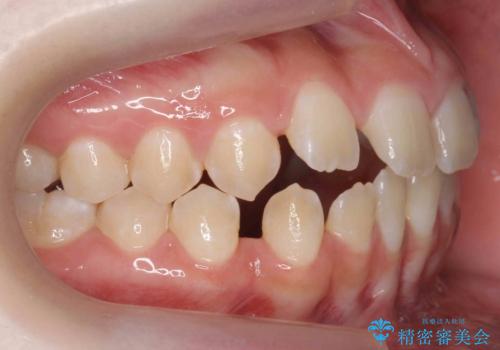

- 前歯の隙間を主訴に来院。

顎の大きさに比べて歯が小さく、隙間が目立っていました。

マウスピース矯正で隙間を閉じる処置を行いました。